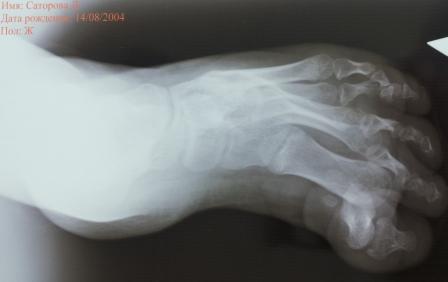

Уважаемый Никита, посмотрите на рентген, проблема не в первом пальце, а кавусе стопы. Скорее всего за счет высокого свода стопы у ребенка затруднение в одевании обуви. Поэтому только капсулотомиия 1 ПФС и апоневротомии будет не достаточно, нужна капсулотомия по Штурму. Но без заднего релиза.

Раньше я бы так не дисскутировал, но неблагоприятные исходы релизов побудили к комплексному подходу. При так называемом маневре Понсети сначала передний отдел выводится по отношению к среднему, продолжая маневр средний отдел выводится по отношению к заднему. Я это к тому что можно вывести передний отдел и исправить кавус, что лучше всего получается при методике Понсети.

Уважаемый Нияз. В очередной раз спасибо за статьи. Придерживаемся того же алгоритма лечения рецидивирующей косолапости: коррекция деформации, задний релиз, транспозиция ПБМ. Все здорово, только в данном случае речь идет не о рецидиве эквино-аддукто-варусного компонента или динамической супинации, а о рецидиве кавуса с формированием пяточной стопы и вывиха в ПФС, положение пятки при этом, как минимум, среднее. Кавус рецидивирует крайне редко и, вероятно, в данном случае является ятрогенным. Что вы предлагаете корригировать в повязках я понимаю, но не вижу необходимости в коррекции у этого пациента- нечего тут корригировать по Понсети. Проблема кавуса есть, но пациента, со слов доктора, беспокоит 1 палец. Кавус мягкотканным релизом у этого пациента не устранить, а резецировать и артродезировать средний отдел рано. Так и предлагаю решать проблему первого пальца.